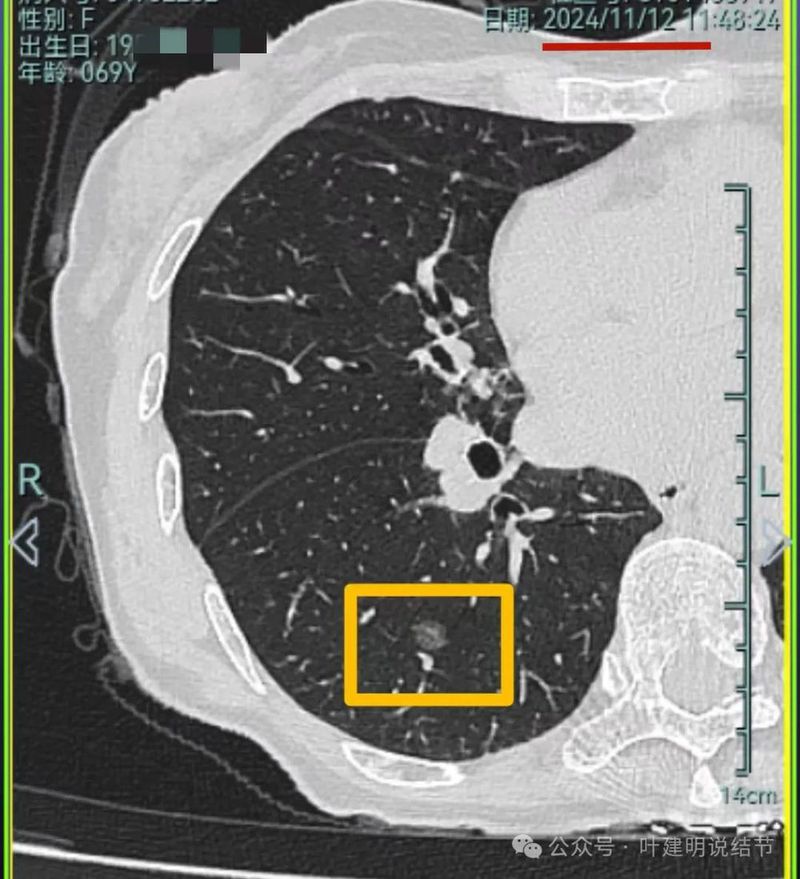

再看2024年11月复查的情况:

病灶4仍钙化且无明显进展。

病灶5实性成分明显较前增多明显,总体上有进展,但这个病灶主要周围比较散,显得有些模糊。

我想我们这样也来考虑问题:1、左侧已经手术的确诊是肿瘤性质,左上已经消融的也是随访持续存在的磨玻璃密度结节,虽然没有病理依据,仍然要考虑广义上来讲的肿瘤范畴,看了以前的片子,从2019年到2023年并没有显著的进展,大概是肺泡上皮不典型增生可能性大。右侧的也有磨玻璃结节与混合磨玻璃结节考虑是肿瘤范畴的。所以总体上两肺多原发早期以磨玻璃为表现的肺癌,整体风险都不大。2019年切除的左肺下叶病灶也是纯磨玻璃密度,其实如果继续随访或者只做楔形切除也并没有什么关系。这说明体质本身或者致病的因素,就是容易长磨玻璃肺癌的,即便把目前发现的都解决,后续仍可能再有新的。原因不明,致病因素仍在。2、右肺上叶红色之处从2019年开始,是逐渐进展的,当然即便是现在,也不是说危险就已经很大,考虑仍然是原位癌或者微浸润性腺癌可能性大;中叶蓝色这处乍一看像至少是微浸润,但前后对比以后发现从2019年到现在,几乎没有显著进展,这样的话慢性炎伴肺泡上皮增生或者伴纤维增生也是有可能的,至少风险并不能认为大;右肺下叶黄色这一处,使纯磨玻璃密度,整体轮廓与边界清楚,考虑是肿瘤范畴的,不典型增生可能性较大,也有可能原位癌,随访稍有进展,风险仍然不大;中叶绿色这处是慢性炎伴钙化的,靠近叶裂的地方也像慢性炎,但此处随访有所进展。不过因为有卫星灶,整体显得比较散,所以虽然恶性可能性较大,但也不能完全除外炎性的可能性。当然如果此灶确实恶性,那风险则相对较其他进展缓慢的要高一些。从目前右侧所在的这些病灶来讲,真正有一定的风险而且最为确切的是红色这处,而且应该也没有到浸润性腺癌或者说不处理会要转移很危险这种程度。3、明确了多原发早期肺癌没有办法预防与控制,也明白了目前已经存在的较明显的这些病灶总体风险的高低。我们再来考虑需不需要近期干预处理。左侧既手术过又消融过,右侧的多发病灶目前又还没有到危险很高的程度,又没有办法预防后续再有新的病灶。我个人偏保守,我觉得仍然可以半年复查随访,如果最具风险的病灶有进展并且不处理可能导致不良后果,到这样的程度再来考虑综合如何处理干预便可。4、假如右侧我们予以处理,上叶红色的以及中叶蓝色的都可以楔切,但绿色考虑良性的再进展或以后像恶性时怎么办?而若中叶切除加上叶楔切,在左侧已经手术过的情况下肺功能影响相对也不小,何况右下比较中间的位置还有桔色这处呢。当然右下这处得考虑消融。所以,我的想法还是能熬再熬下,待其他监测有变化再通盘考虑。意见供参考!